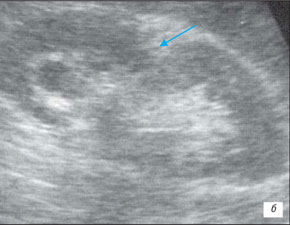

Ехограма нирки

а – запальні зміни в нирці;

б – втягнення на контурі нирки (стрілка)

На данній ехограмі ми помічаємо чіткий патологічний осередок ураження сечоводів, їх розмірів і глибину залягання.